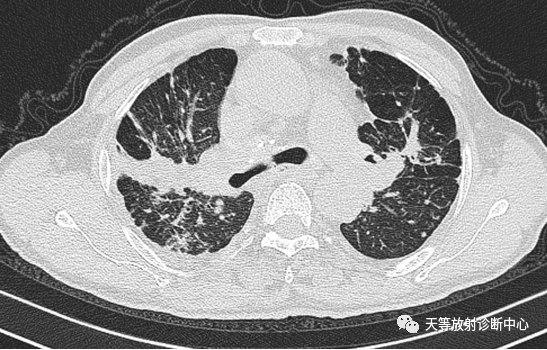

▲右肺大片状实变影,肺炎型肉芽肿组织,肺内播散病灶。

▲两肺大片状实变影,肺炎型结核;